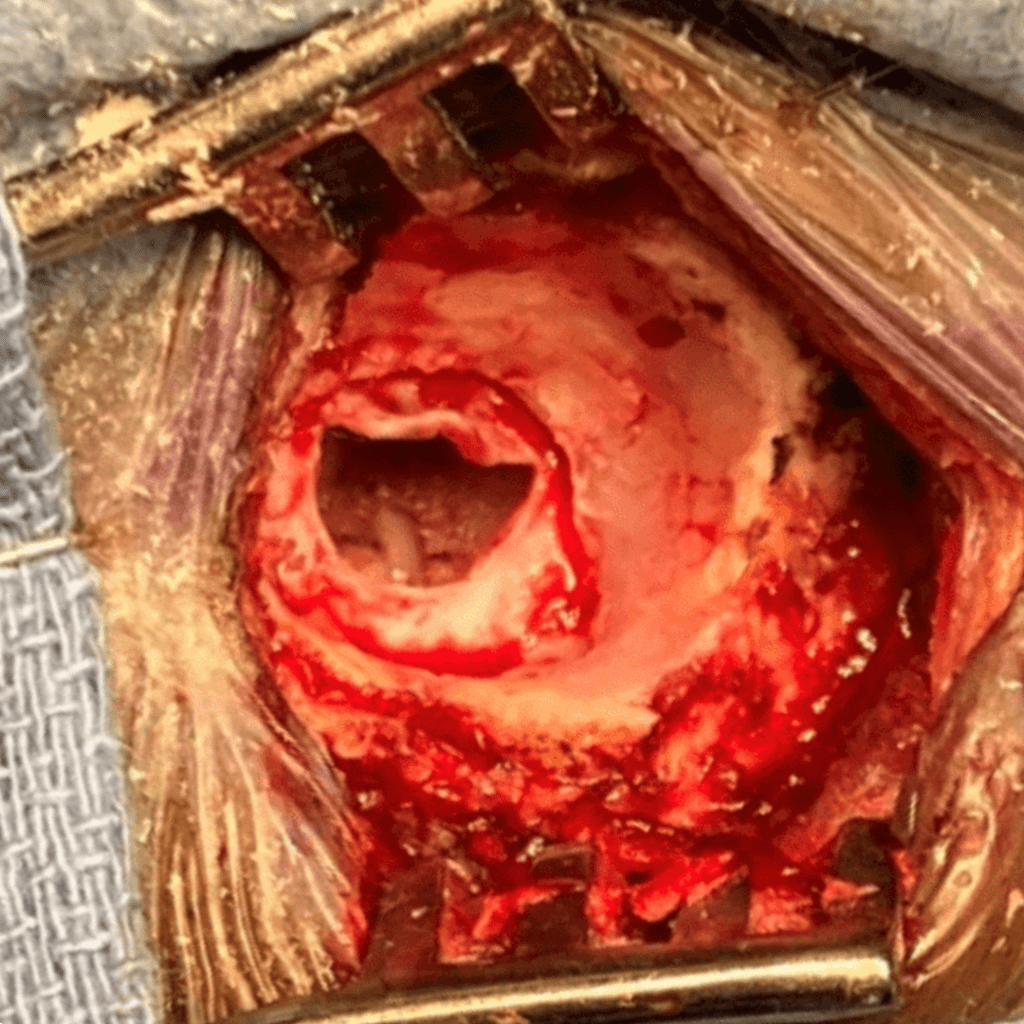

In my hands, the MVD usually takes about 2 hours once the operation has started. It is performed under general anesthesia, with the patient in the lateral position. Neuro-monitoring is performed throughout the case. A one-and-a-half-inch linear incision is made just behind the ear. A circular piece of bone is drilled out about the size of a quarter (Figure 1). The dura is opened up to the transverse – sigmoid sinus junction, and cerebrospinal fluid is released until the brain is fully relaxed (Figure 2). The microscope is brought in to provide both excellent lighting and magnification. Arachnoid dissection is performed so the vascular conflict against the nerve can be clearly visualized. Sometimes, the endoscope can also be used to clarify the anatomy.